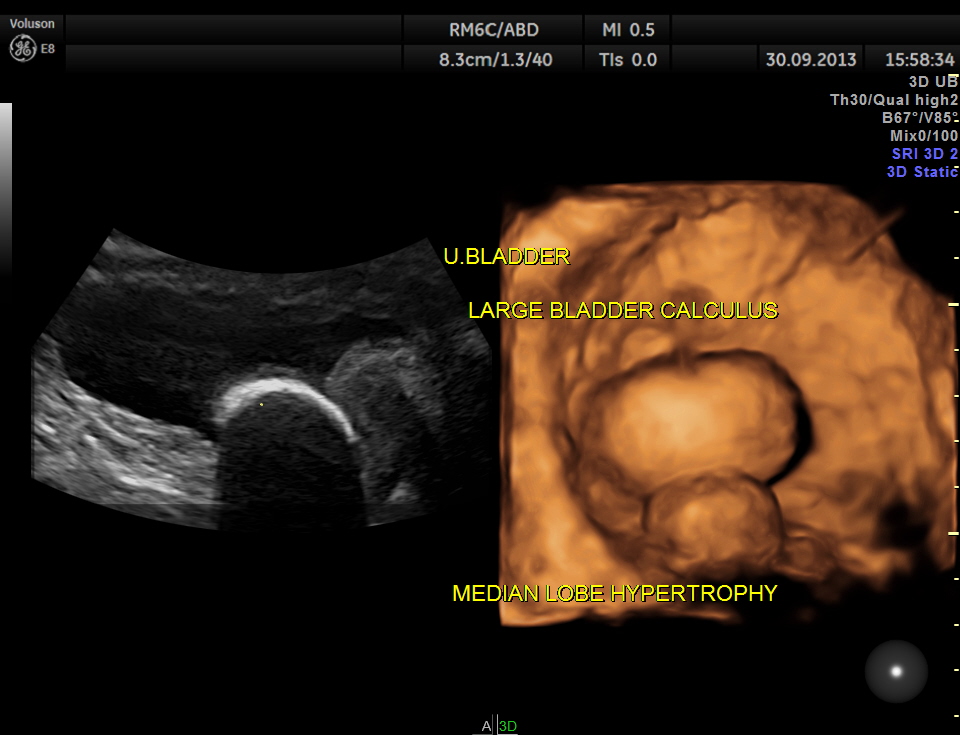

urinary bladder showed a large calculus and prominent swelling of the median lobe of the prostate.

the following images show the 2 d and 3 d appearance of the same.

2 D and 3 D of the bladder calculus alone.

The diagnosis given was Large calculus in the urinary bladder , Severe prostatic enlargement with prominent median lobe hypertrophy , causing Right sided obstructive uropathy.

The diagnosis was made with the 2D images , but the 3 D images were very helpful in explaining to the patient.